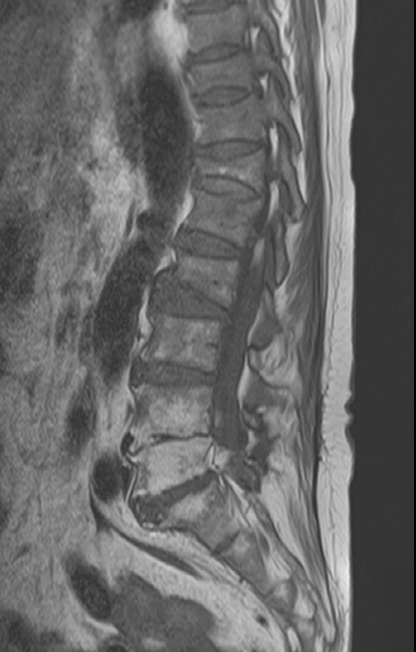

-L Spine MRI

-심한 과호흡 상태에서 검사 시행

-검사 도중 계속 움직임

-Motion Artipact 심하여 scan time 짧게 조정함.

- post L4-5 laminectomy

- flattening of T10 through L2 bodies with partially fatty bone marrow and some sclerotic change

- herniation of discs T10-11 through T12-L1 discs into adjacent vertebral bodies

- L2-3, L3-4 and L5-S1 diffuse bulging discs and ligamentum flavum thickening with indentation of thecal sac and encroachment on neural foramens

- some CSF effacement of L2-3 and L3-4 thecal sac

- partial to circumferential perineural fat effacement of left L5-S1 neural foramen

- decreased T2 signal intensity of discs with osteophytes

1. old T10 through L2 compression fracture with schmorl's nodes

2. L2-3, L3-4 and L5-S1 diffuse bulging discs

3. mild L2-3 and L3-4 central stenosis

4. moderate stenosis of left L5-S1 neural foramen

5. degenerative spondylosis